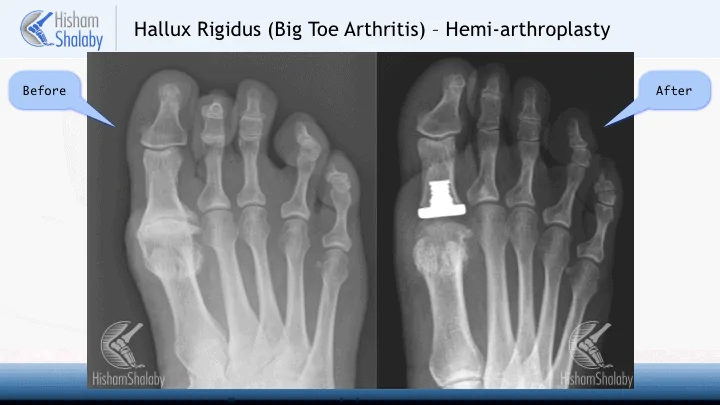

The gold standard treatment of the advanced wear and tear in the big toe joint remains the fusion. However, the fusion causes loss of the movement completely and can leave the patient with some limitations. The recovery after the fusion also usually takes a bit longer as we wait for the 2 sides of the joint to heal together.

The replacement was therefore thought of as an alternative is selected cases. The full replacement of the joint has yielded discouraging results in the literature. It also entails resection of a lot of bone and therefore makes any future surgery in this area more difficult.

The hemi-arthroplasty means replacement of only half the joint. We are performing more of this procedure now with very good results in selected cases